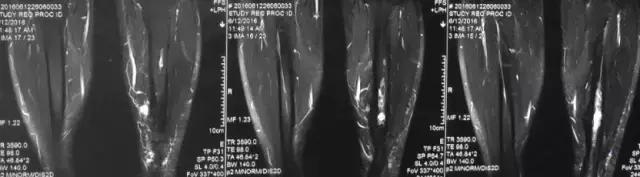

影像检查

核磁示中下段骨髓炎,上面切口处流脓,请问张主任你的意见要上手术吗?

诊断:感染。 检查:膝关节MRI,确认伤口窦道是否与髓腔相通。 治疗:1、血沉和C反应蛋白正常,目前无需特殊处理。 2、如果窦道反复出现或血沉和C反应蛋白升高可考虑手术。如证明窦道与髓腔相通,需行扩髓。